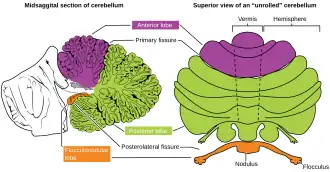

The posterior lobe of cerebellum or neocerebellum is one of the lobes of the cerebellum, below the primary fissure. The posterior lobe is much larger than anterior lobe. The anterior lobe is separated from the posterior lobe by the primary fissure, and the posterolateral fissure separates flocculonodular lobe from the posterior lobe.[1]